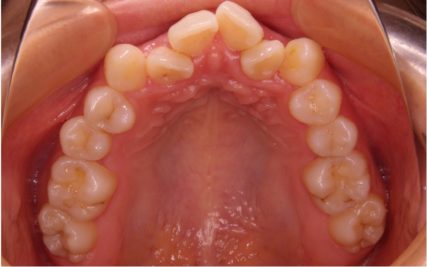

でこぼこ/20代女性

- 不正咬合/叢生(でこぼこ)

- 上下とも前歯のスペース不足が認められた。歯のサイズと顎の幅とのバランスが不調和な事が原因の1つとして考えられる。

- 上顎両側4番・上顎両側8番・下顎両側4番・下顎両側8番抜歯

- 前歯部のでこぼこが解消され、正常咬合を獲得する事が出来た。又、歯科矯正用アンカースクリューを用いる事で抜歯スペースを有効に利用できた。